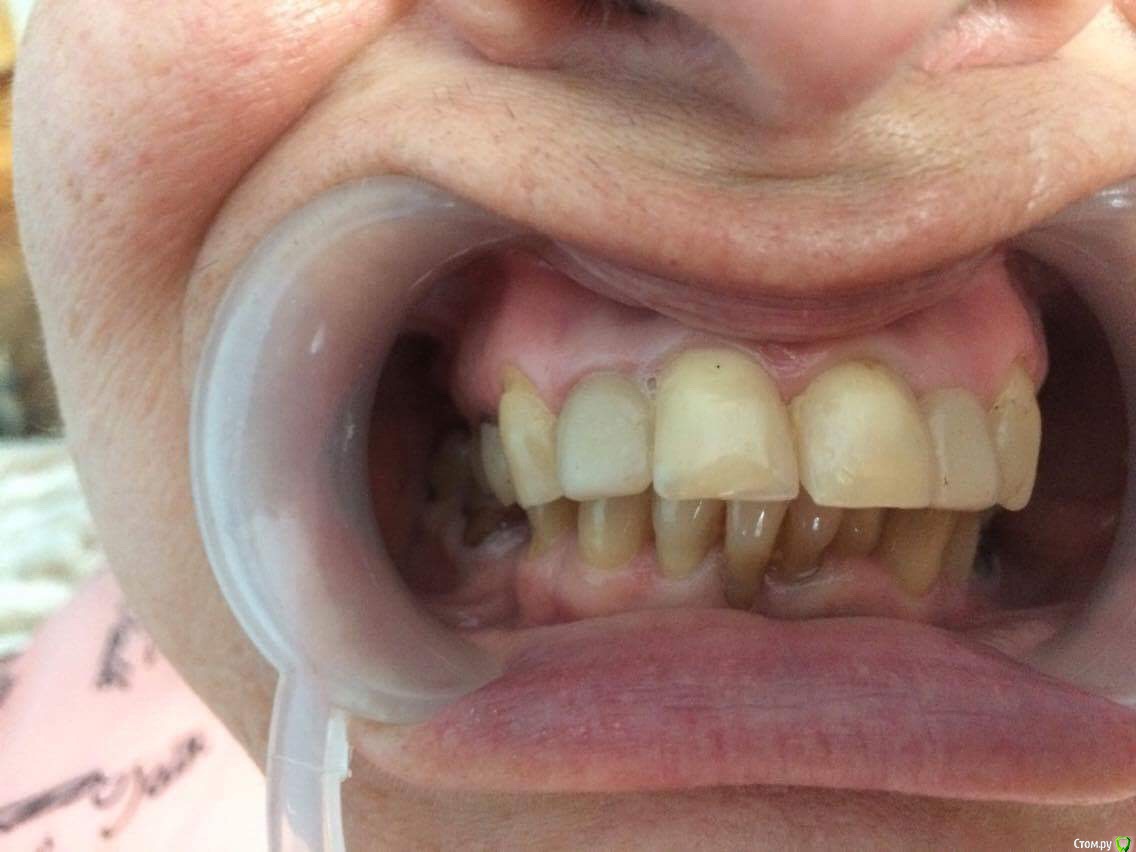

dr.Dre Опубликовано 27 июня, 2017 Поделиться Опубликовано 27 июня, 2017 Добрый день коллеги тему уже создавал но дал мало информации ,пациентка 58 лет .Помогите составить план лечения,имплантацию не потянет .Нужно ли здесь поднимать прикус? Ссылка на комментарий

dr.Dre Опубликовано 27 июня, 2017 Автор Поделиться Опубликовано 27 июня, 2017 Док,фотопротокол вам мягко говоря подтянуть надо, боковые вообще не видно.Про имплантацию мы поняли,а остальное?Устраивает ли ее эстетика фронта,или просто хочет чтобы было чем жевать в боковом отделе?Как к съемному протезированию относится,потому что иначе вы 3 сегмент не закроете.Плюс вы же понимаете,что если вы прикус поднимете,то автоматически под коронки/виниры/накладки пойдут все зубы,включая интактный нижний фронт и витальные верх это вы с пациенткой обсудили? Может после этого уже и на имплантацию мотивация появится?Эстетика не устраивает,пациент хочет все делать полностью ,к сьемному относиться отрицательно.Хочет ровные красивые зубы Ссылка на комментарий

chervoncevdaniil Опубликовано 27 июня, 2017 Поделиться Опубликовано 27 июня, 2017 (изменено) Ну в таком случае я не знаю как вы будете низ боковые сегменты протезировать,но 36 однозначно под удаление,26 и 27 в связи с деформацией плоскости видимо тоже придется,47 и 17 под вопросом и у нее получаются концевые дефекты.Опять же повторюсь,очень плохо видно что в боковом отделе,но настолько прикус вы навряд ли поднимете,чтобы и боковые зубы остались и при этом фронт не получился как у лошади,потому что по размерам резцы и клыки абсолютно нормальные Изменено 27 июня, 2017 пользователем chervoncevdaniil Ссылка на комментарий